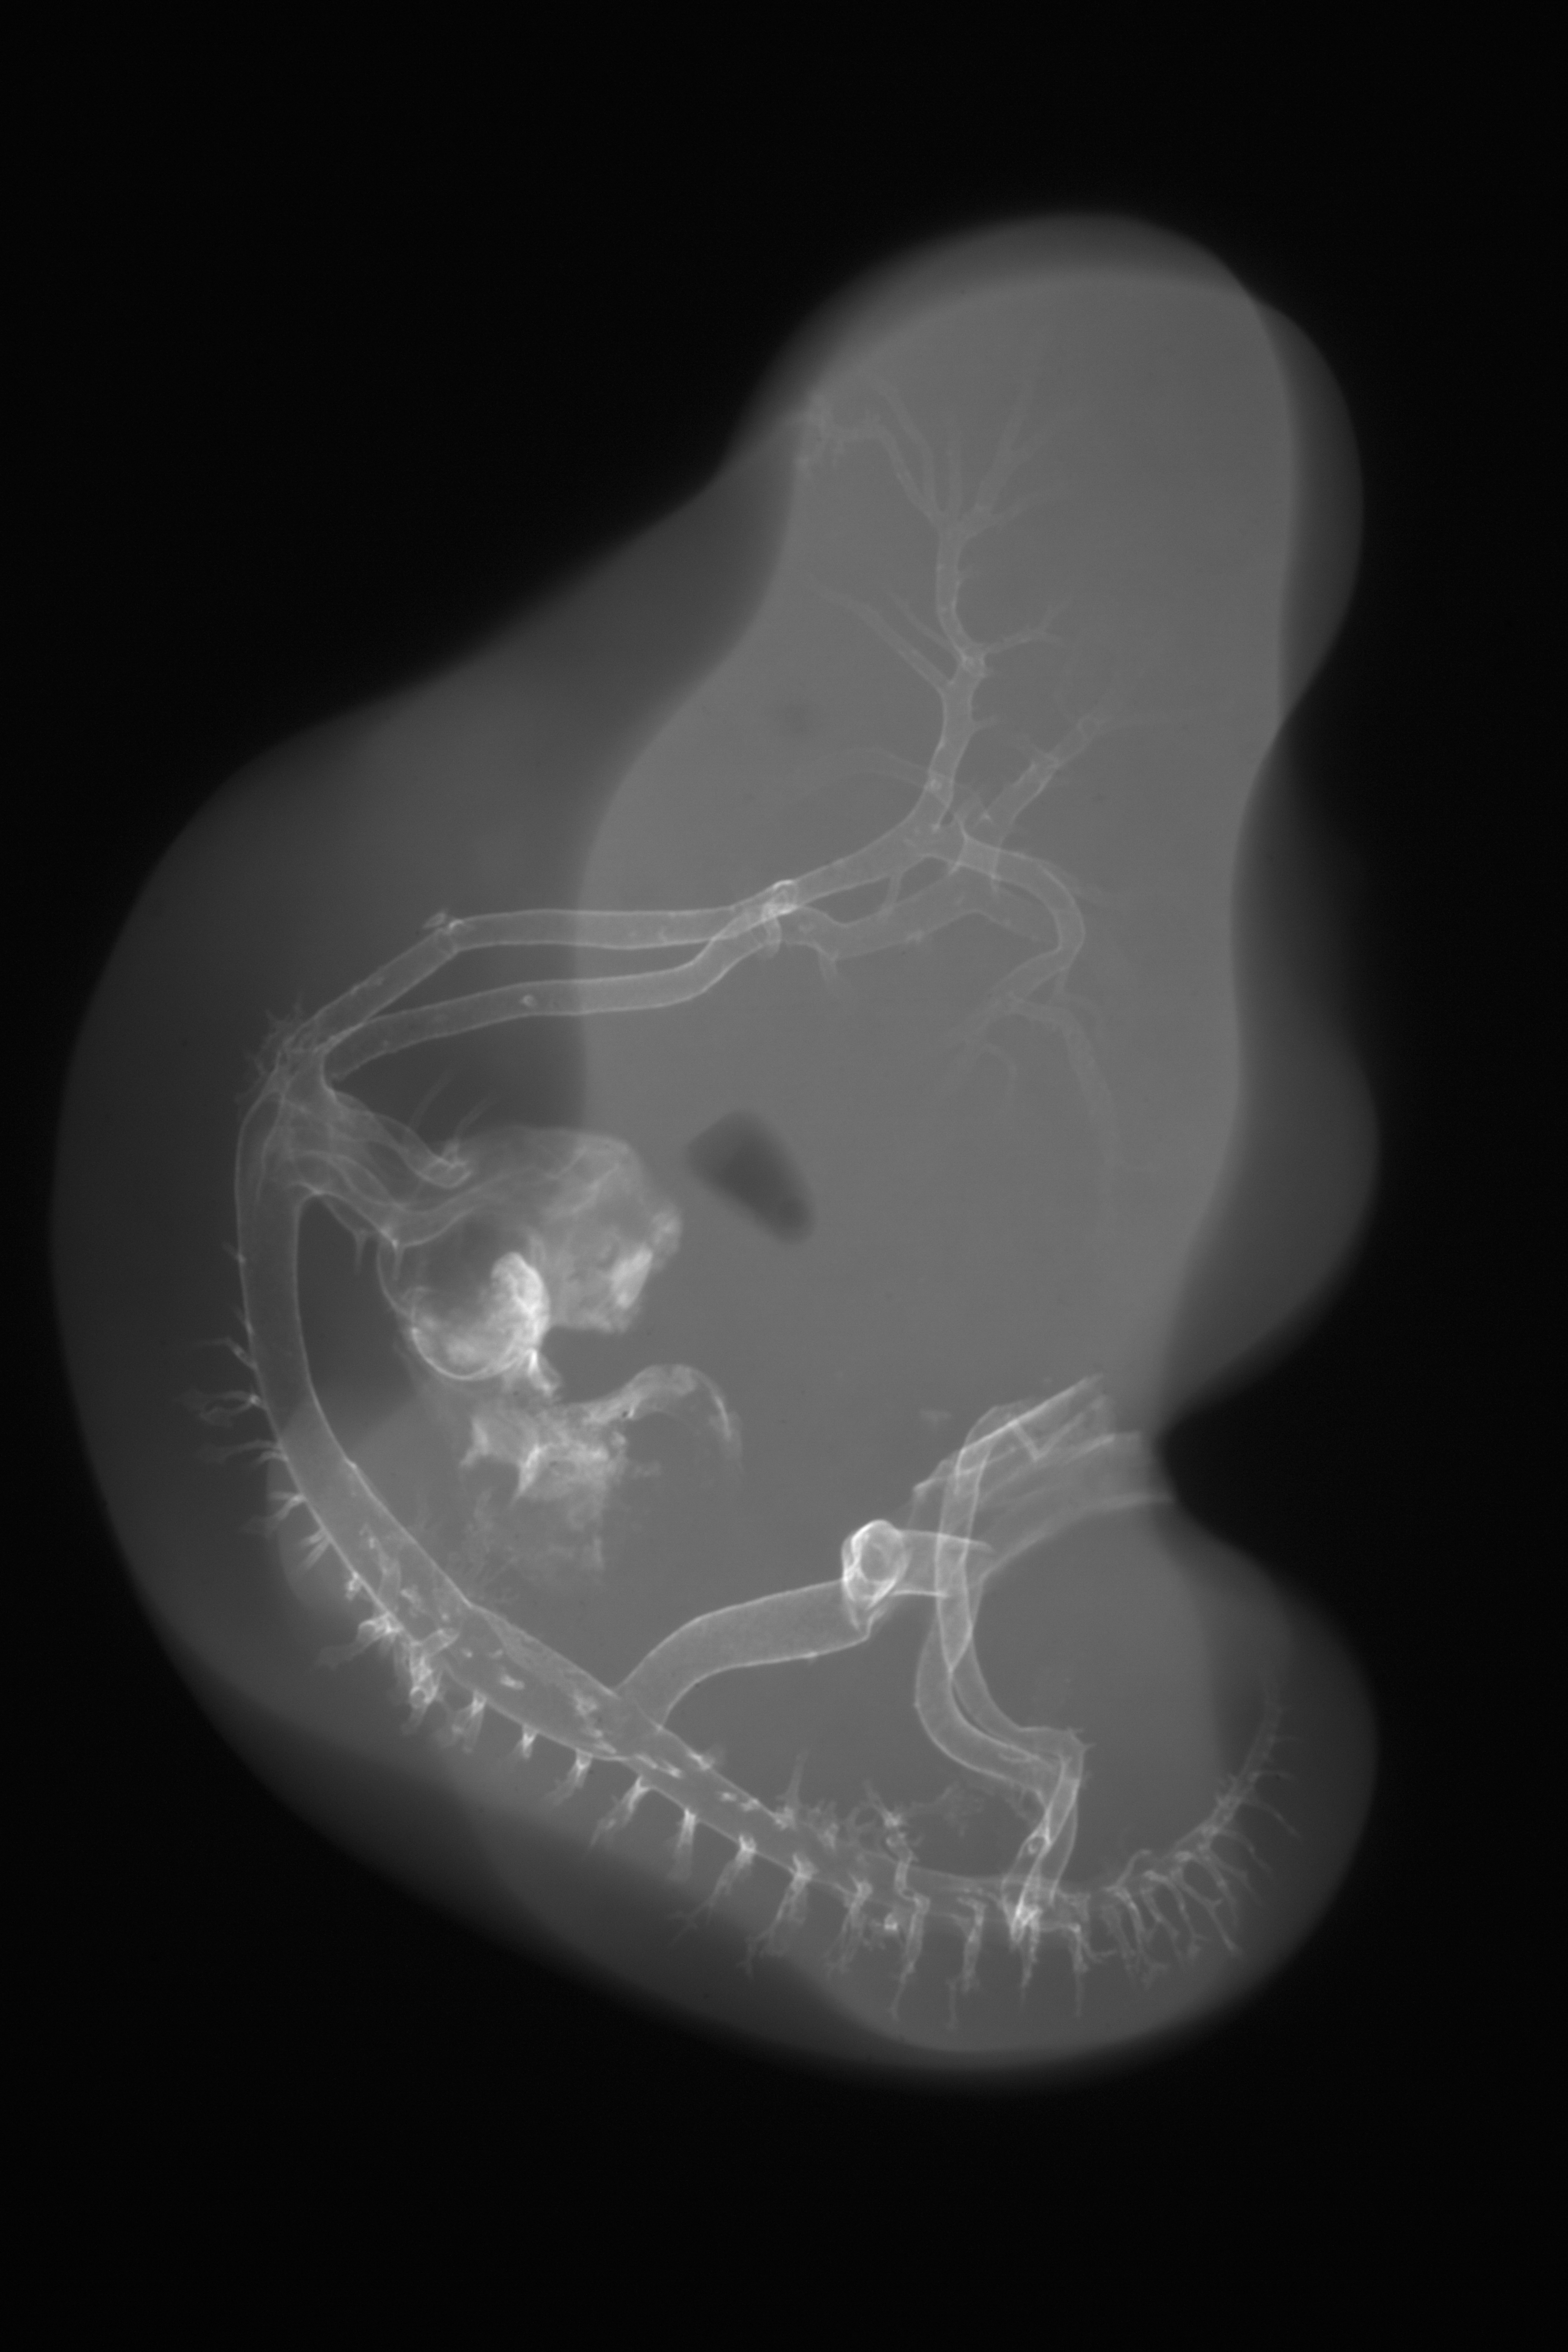

Hamburger-Hamilton (HH) Stage 26 (approx. 5 days)

X-Ray Micrographs